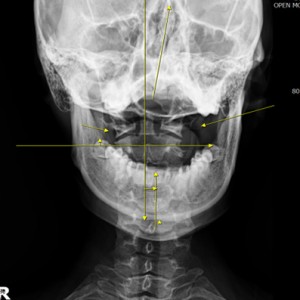

안면 균형검사

턱의 다양한 각도 사진 촬영

X·Y·Z축을 바로 잡는 안면비대칭 3D 입체교정

미간, 콧대, 턱, 목선 맞추기

눈썹 높이 수평

입꼬리 수평

두상 위치 균형

어깨 비대칭 개선